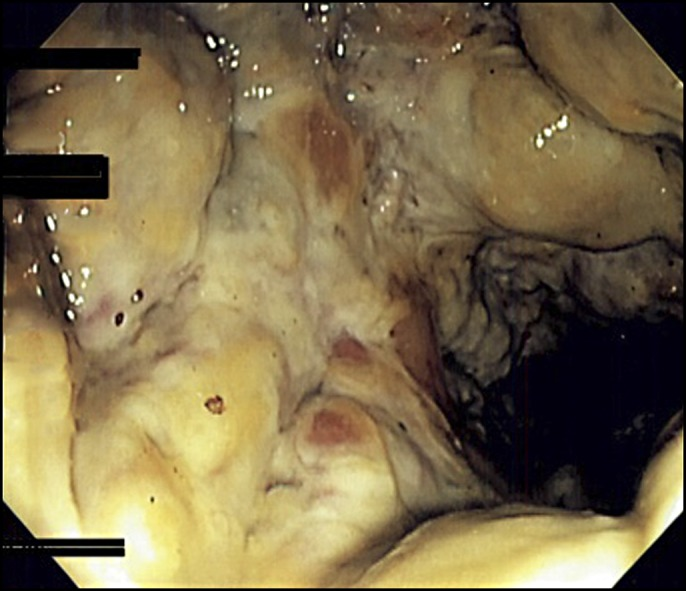

Tổn thương viêm mức độ nặng ở đại trực tràng sau thụt cà phêTổn thương viêm mức độ nặng ở đại trực tràng sau thụt cà phê